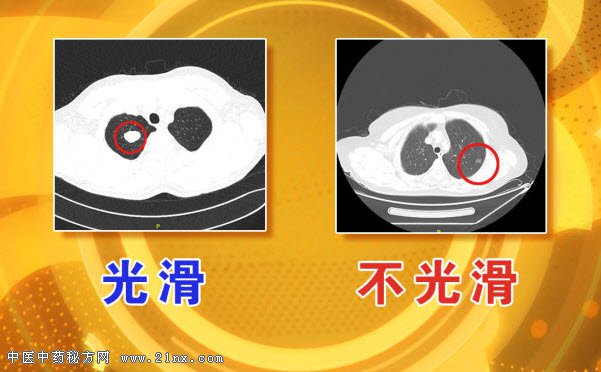

图:肺部结节光滑与不光滑